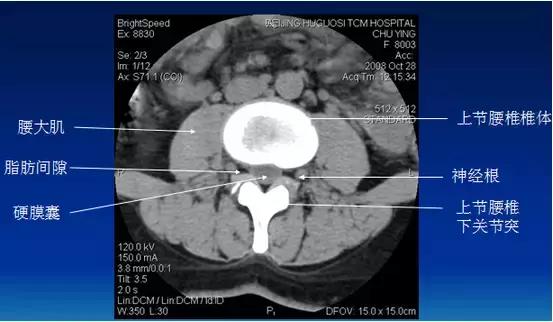

常规腰椎CT扫描层面

常规腰椎CT扫描L3-S1段,分为

(1)椎体层面(骨窗):观察椎体、附件骨质。

(2)椎间盘层面(软组织窗):观察椎间盘、硬膜囊、神经根、韧带等软组织。